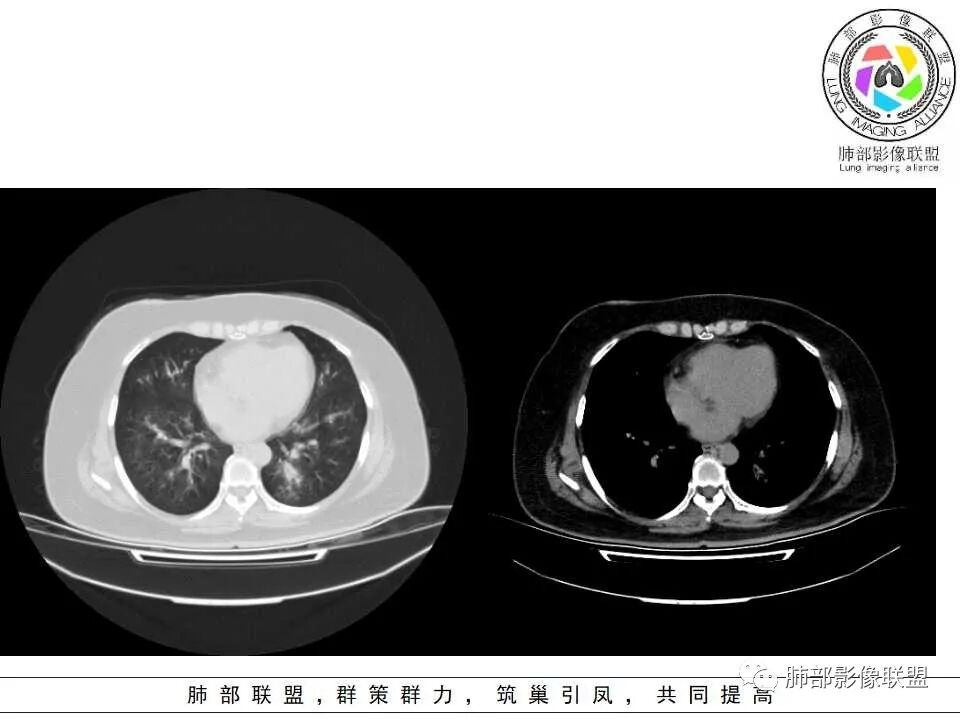

1.病灶沿支气管分布的特点相当明显,相应支气管壁广泛增厚。这种与支气管关系极为密切的片影和/或结节影,常高度提示气道相关感染,如支气管肺炎。

2.患者两肺多发病变,具有广泛性。如此广泛分布更多见于免疫低下的机会性感染。

3.支气管壁广泛增厚对气道侵袭性曲霉病具有一定的提示意义。注意患者没有支气管扩张,临床也未提供IGE等实验室资料。

4.老年女性患者,咳嗽少痰,伴喘息气短8天。注意患者没有发热,中毒症状不明显。既往糖尿病、高血压病史。

炎性指标升高,头孢等药物覆盖疗效不佳。

白细胞升高异乎寻常,注意病史已有两年之久,这至少提供两方面信息:

1)与本次肺部感染不能直接密切对应或相关联,能想象吗,这样的感染持续两年?

2)患者存在血液系统疾病的可能性,如白血病,这应当进一步查实。

1.器官支气管管套样壁增厚和/或支气管扩张,注意壁增厚较均匀,和/或伴有播散性小片影及结节影,注意这些小片影或结节影边界有时较普通炎性病灶清楚。

2.可以阻塞支气管造成肺不张而酷似中央型肺癌。偶而可呈大范围毛玻璃样影。

3.易形成空洞,常无液平面。注意哪些一两周内出现的多发空洞病灶,形成空洞也往往靠边。